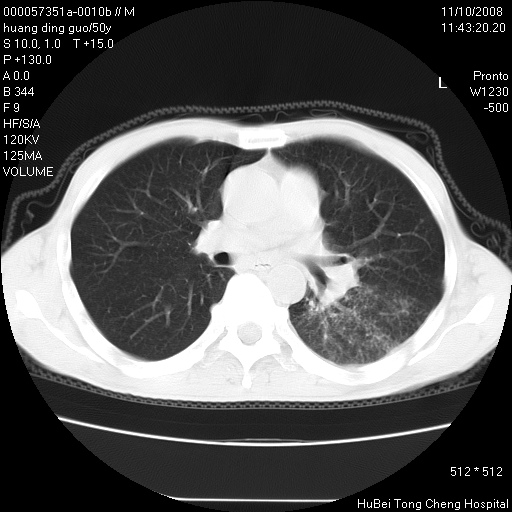

患者 男,50岁。左侧腰背部疼痛3月余,伴消瘦。平素健康,无传染病史。

胸部ct轴位平扫(层厚10mm,螺距1.5,重建间隔10mm),图像如下:

左肺下叶背段有一厚壁空洞,外壁呈锯齿状伴毛刺改变。空洞相邻胸膜有牵拉改变。左肺下叶血管支气管束不规则增粗,小叶间隔增厚。胸椎骨质破坏。考虑左肺下叶周围型肺癌伴左肺下叶癌性淋巴管炎、胸椎转移。

左肺下叶背段有一厚壁空洞,外壁呈锯齿状伴毛刺改变。空洞相邻胸膜有牵拉改变。左肺下叶血管支气管束不规则增粗,小叶间隔增厚。胸椎骨质破坏。考虑左肺下叶周围型肺癌伴阻塞性肺炎、胸椎转移。其他待排

左肺下叶背段有一厚壁空洞,内壁不规则,外壁呈锯齿状伴毛刺改变。空洞相邻胸膜有牵拉改变。周围呈絮状炎性改变,左肺下叶血管支气管束不规则增粗,小叶间隔增厚。胸椎骨质破坏。考虑左肺下叶周围型肺癌伴左肺下叶阻塞性肺炎、胸椎转移。